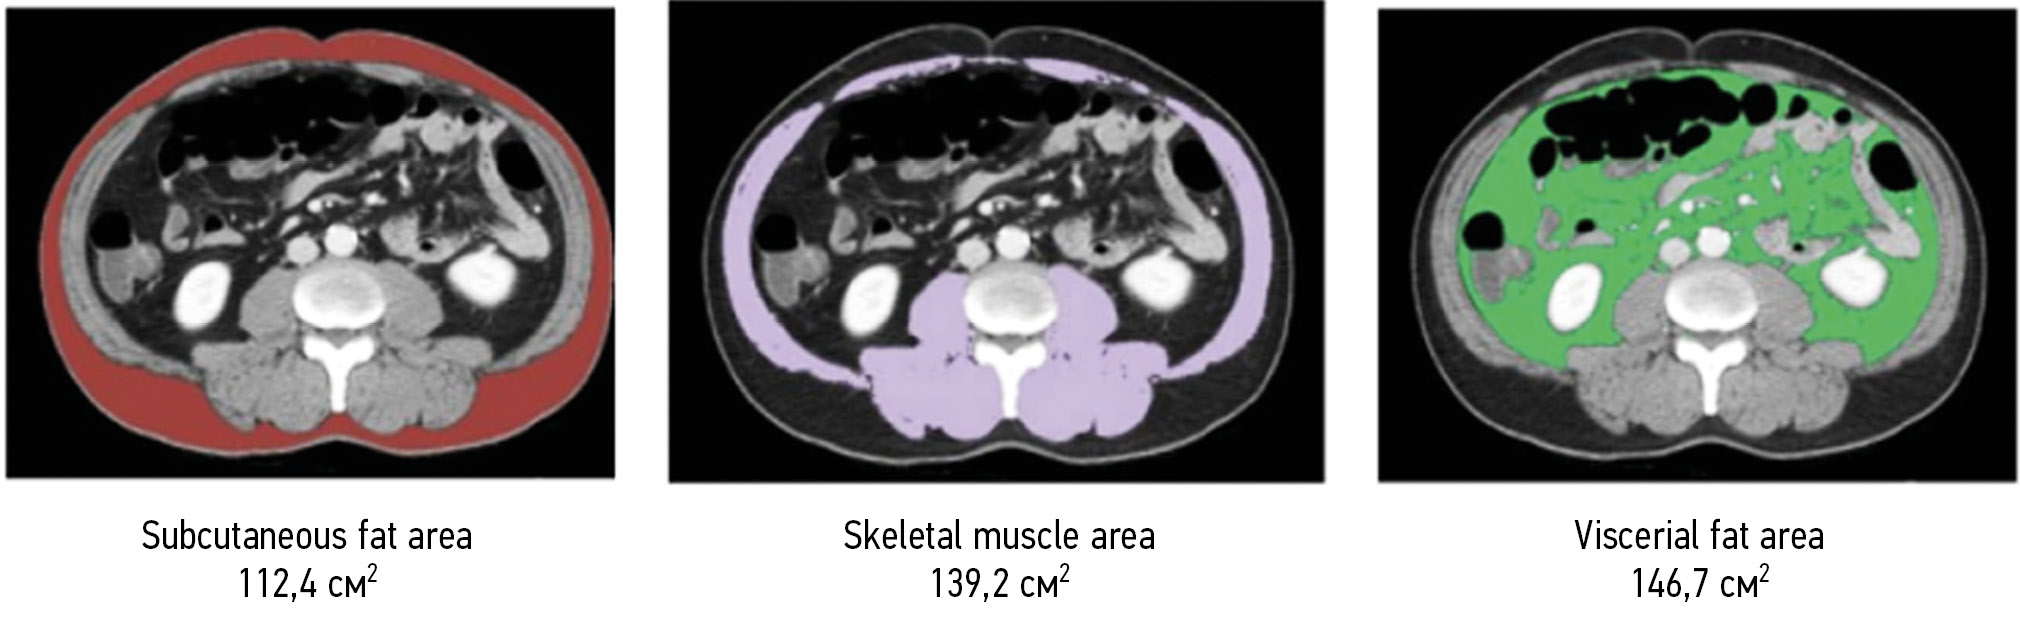

在图2显示了通过人工智能算法测量L3水平的切片中夹有的肌肉组织、皮下脂肪组织和内脏脂肪组织面积的变体。

*图2使用J. Ha等人[46]的L3SEG-net AI算法在L3水平上对测量肌组织的、皮下脂肪组织和内脏脂肪组织进行切片的面积测量实例(单位:cm2)。自左而右用红色标记皮下脂肪组织,用紫色标记骨骼肌肉量,用绿色标记内脏脂肪组织。

*可以在Creative Commons Attribution 4.0 International License (CC BY 4.0), Scientific Reports上找到。